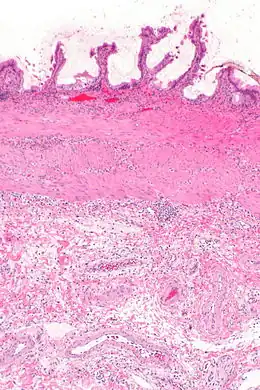

La cholécystite est liée à l'infection du liquide vésiculaire, suite le plus souvent à l'obstruction du canal cystique par un calcul biliaire : le liquide en stase, d'abord stérile, provoque une inflammation locale qui peut se surinfecter alors, le plus souvent avec des germes digestifs présents dans le duodénum. Si elle n'est pas prise en charge convenablement, la vésicule biliaire peut se gangréner et provoquer une péritonite.

L'échographie hépatique montre une lithiase avec un aspect de cône d'ombre. Il existe un épaississement de la paroi de la vésicule biliaire, qui peut prendre un aspect feuilleté. La sonde d'échographie, passant au niveau de la vésicule, provoque la douleur (on parle donc de « Murphy échographique »). Ces signes sont très sensibles et spécifiques[4]. C'est l'examen fait en première intention.